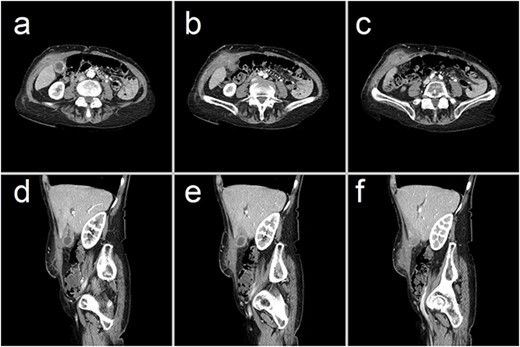

She represented 10 weeks later, complaining of pain at the previous surgical site. Remarkably, removal of the overlying wound dressing revealed a 20 mm gallstone lodged at the external opening of a CCF that had, by then, epithelialized along the previous drain tract (Figs 2 and 3). This obstructing gallstone and multiple others were removed from the visible fistula tract at the bedside using forceps.

Representative CT images showing (a–c) axial and (d–f) sagittal views of the CCF, forming a communicating tract that extends from the gallbladder fundus, through the anterior abdominal wall and onto the skin. There has been interval collapse of the gallbladder, whose wall remains thickened with mucosal hyperenhancement, in keeping with chronic cholecystitis. Hyperenhancing gallstones are visible along this fistula tract.